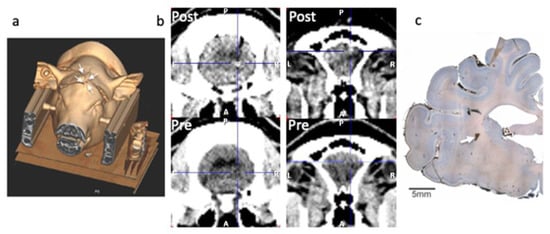

- Bjarkam, C.; Cancian, G.; Larsen, M.; Rosendahl, F.; Ettrup, K.; Zeidler, D.; Blankholm, A.; Østergaard, L.; Sunde, N.; Sørensen, J. A MRI-compatible stereotaxic localizer box enables high-precision stereotaxic procedures in pigs. J. Neurosci. Methods 2004, 139, 293–298. [Google Scholar] [CrossRef] [PubMed]

- Glud, A.N.; Bech, J.; Tvilling, L.; Zaer, H.; Orlowski, D.; Fitting, L.M.; Ziedler, D.; Geneser, M.; Sangill, R.; Alstrup, A.K.O.; et al. A fiducial skull marker for precise MRI-based stereotaxic surgery in large animal models. J. Neurosci. Methods 2017, 285, 45–48. [Google Scholar] [CrossRef] [PubMed]